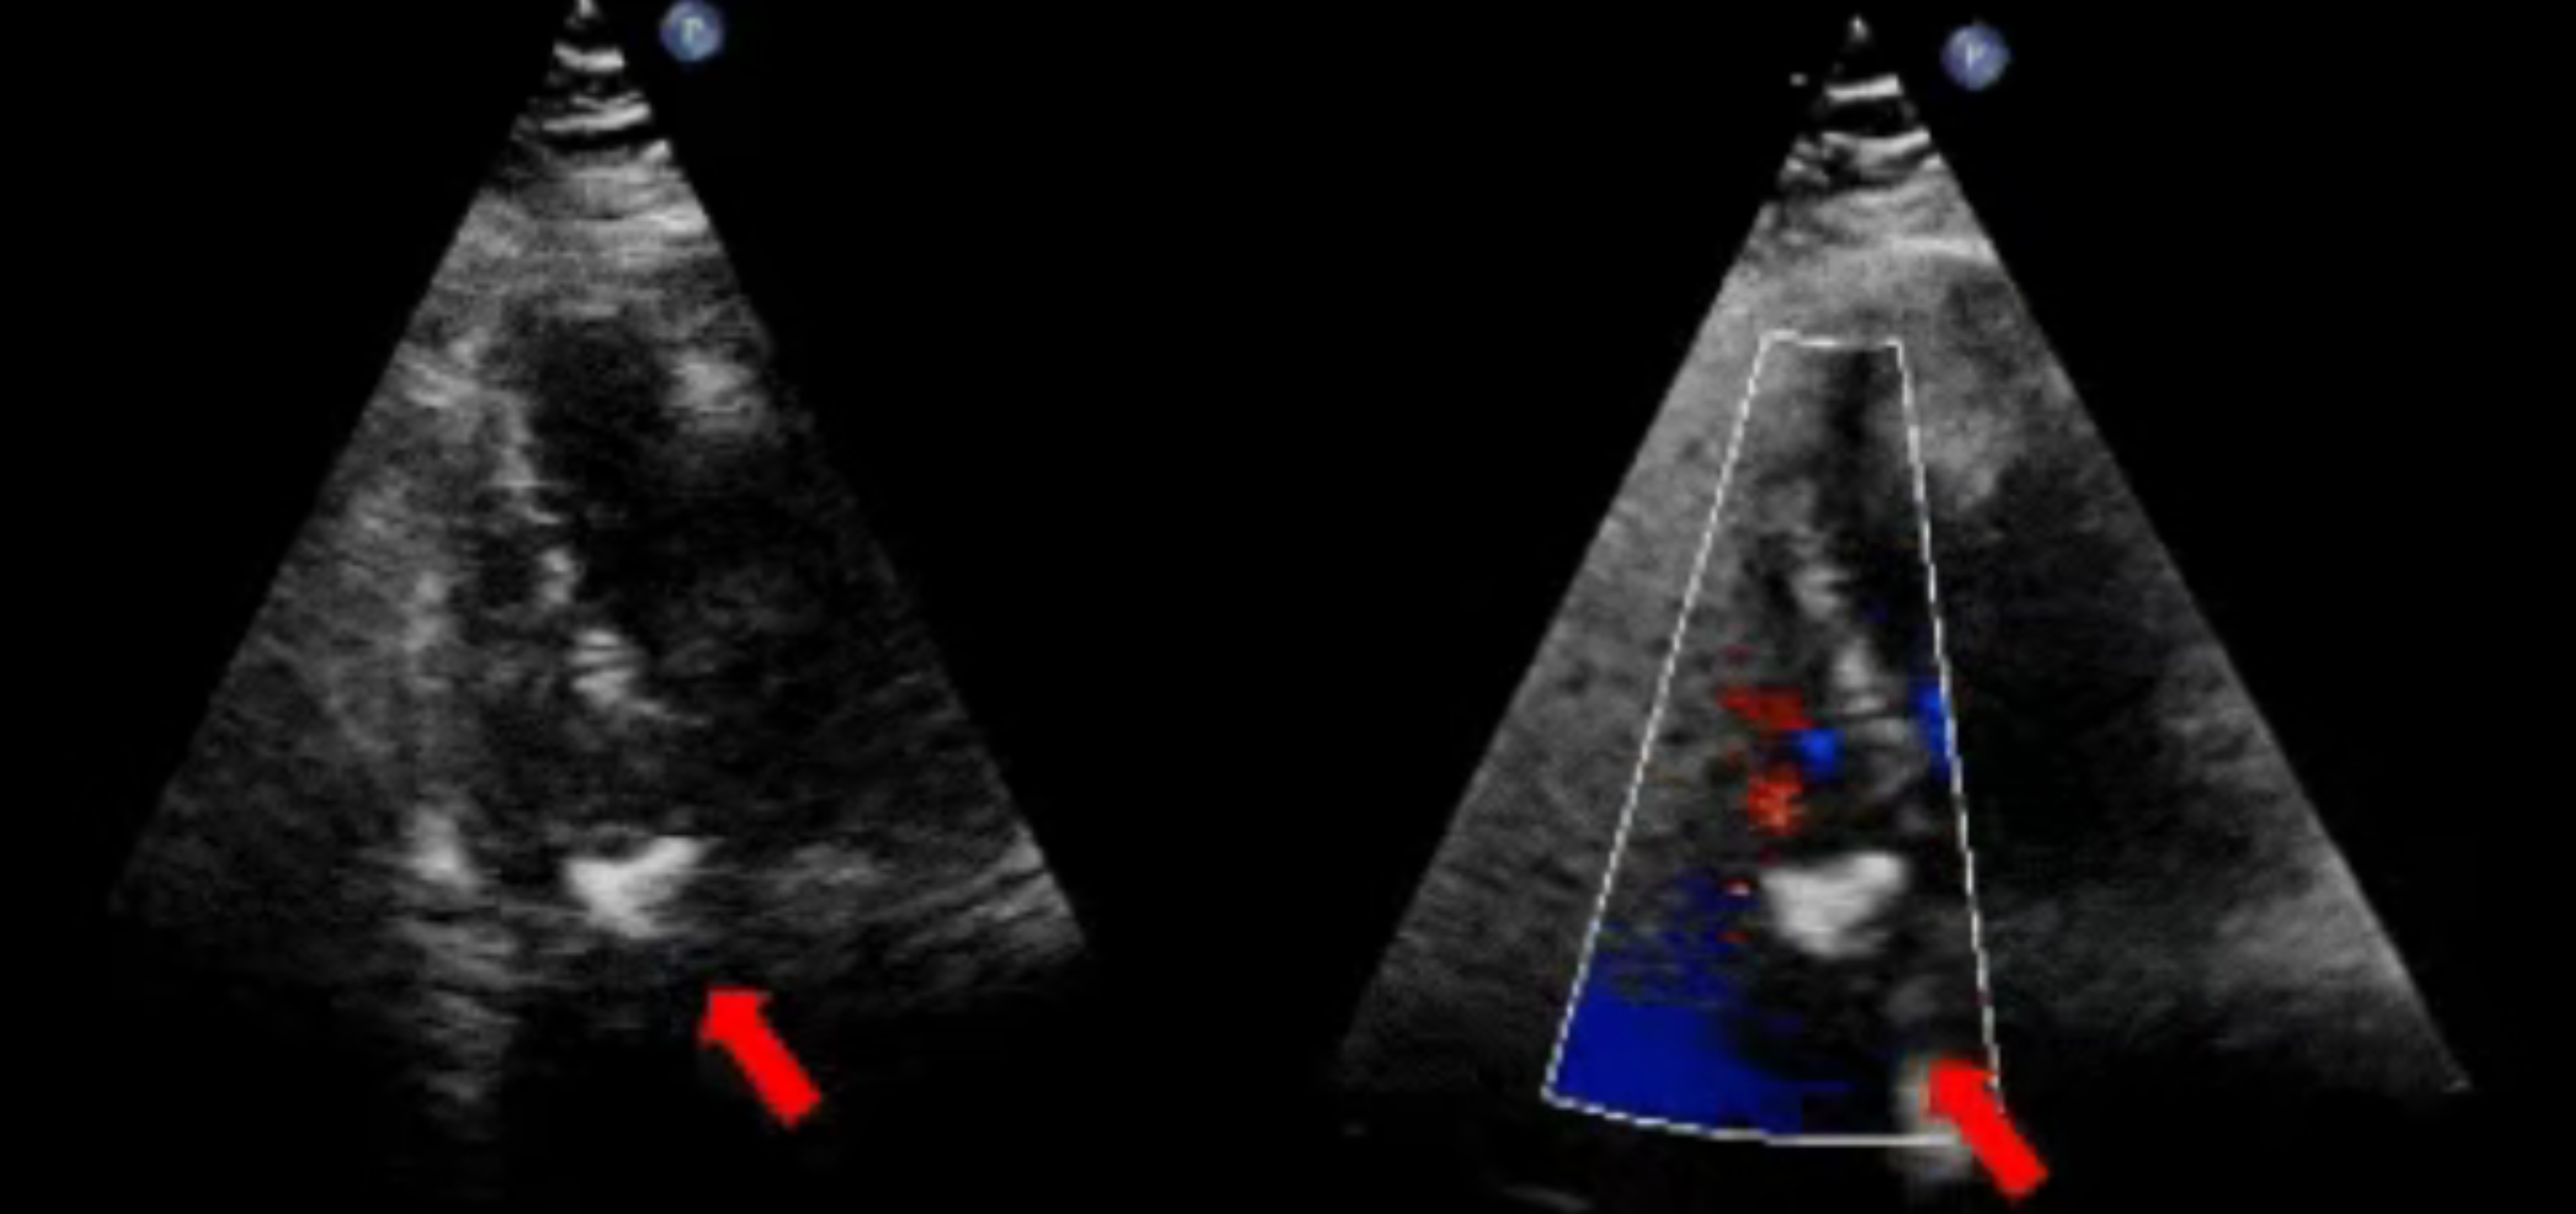

合并膨出瘤PFO患者术后超声

无放射线经皮介入技术(超声引导经皮介入技术)是阜外团队世界首创的心血管疾病介入治疗新方法,该技术单纯采用超声引导器械从外周血管进入心脏,远距离操作器械治疗心血管疾病。实现了"不开刀,无放射线,甚至在患者清醒状态下治疗心脏病“。不但消除放射线等医源性损伤,将手术适应症扩大到危重患者,而且提高了医疗服务的可及性,将心脏手术从要到大城市、大医院找大医生做的“重大手术”转变成“门诊手术,甚至“上门手术”,为医疗资源贫瘠的国家和地区解决了致命的可及性问题。该技术以“降低成员国医疗服务能力差异”的巨大贡献获得“世界卫生组织科技创新奖”,并被联合国评选为全球推广的医疗项目,获得联合国资金及全球体系的支持进行推广。